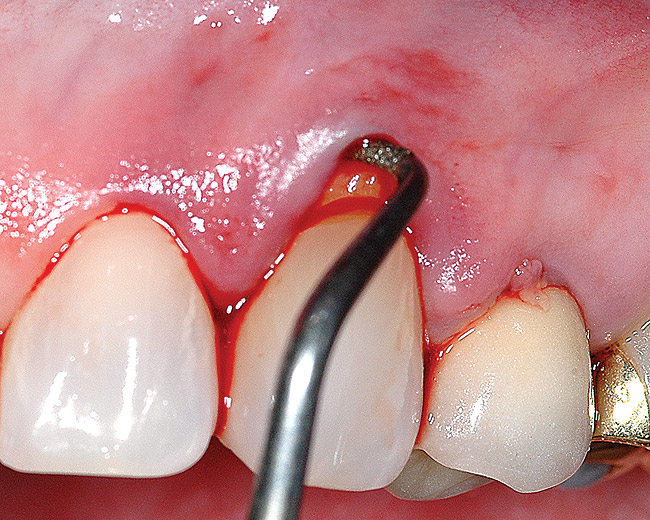

Fig 3 and Fig 4. After mobilization of the marginal tissue, the sharp margins of the lesion were flattened and the enamel overhang was beveled.